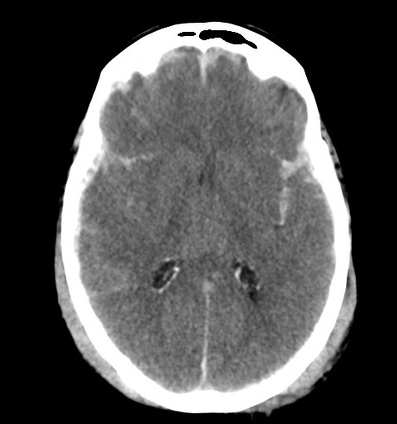

What does a stroke look like on imaging?

CT: bleed will show up as bright white with possible mass effect, ischaemia won’t show up early on but as it establishes it becomes hypodense